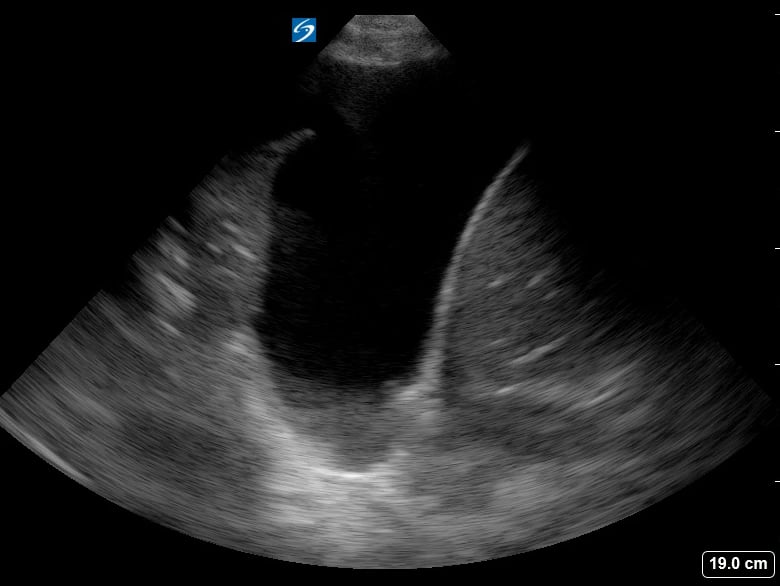

The “spine sign” in lung ultrasound refers to the abnormal visualization of the vertebral bodies above the diaphragm, a key indicator of pleural effusion. Normally, the air-filled lungs obscure the spine above the diaphragm. However, in the presence of fluid, sound waves can travel through the effusion, allowing the spine to be seen. This finding is crucial for diagnosing fluid accumulation in the thoracic cavity.

Recognizing the spine sign is essential for medical professionals using point-of-care ultrasound. Its presence confirms a significant pleural effusion, guiding further diagnostic and therapeutic interventions. This simple yet powerful ultrasound sign enhances rapid assessment in emergency and critical care settings, improving patient management.